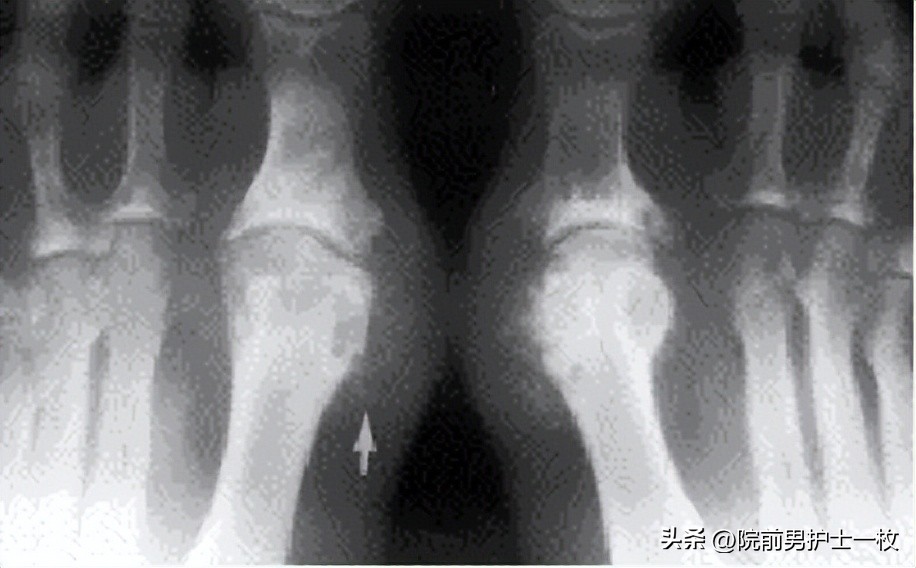

疼痛部位:第一跖趾关节最为常见